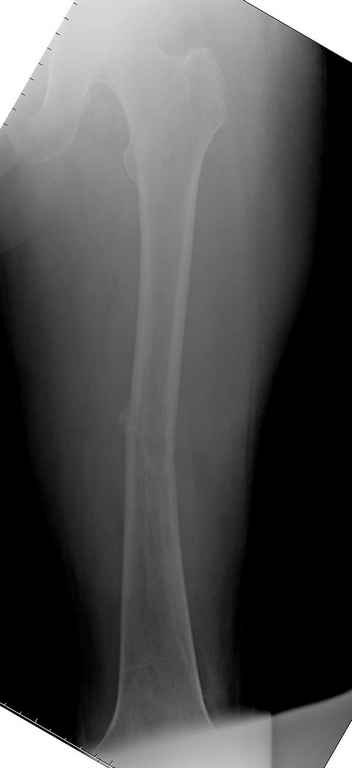

Здесь случай 66 летней пациентки со спонтанными болями в левой нижней конечности, обратилась в приемное, сделаны снимки бедра и КТ.

Патологический перелом бедра, конечность на вытяжении.

Со слов, больная ничем не болела, только последние 3 месяцев чувствовала боли в бедренной области. КТ брюшной полости подтвердил увеличенную правую почку. (5-6)

С минимальным рассверливанием и ретроградным методом провели остеосинтез бедра 12 мм гвоздем. (17-20)

Кровопотеря во время операции меньше 100 мл.